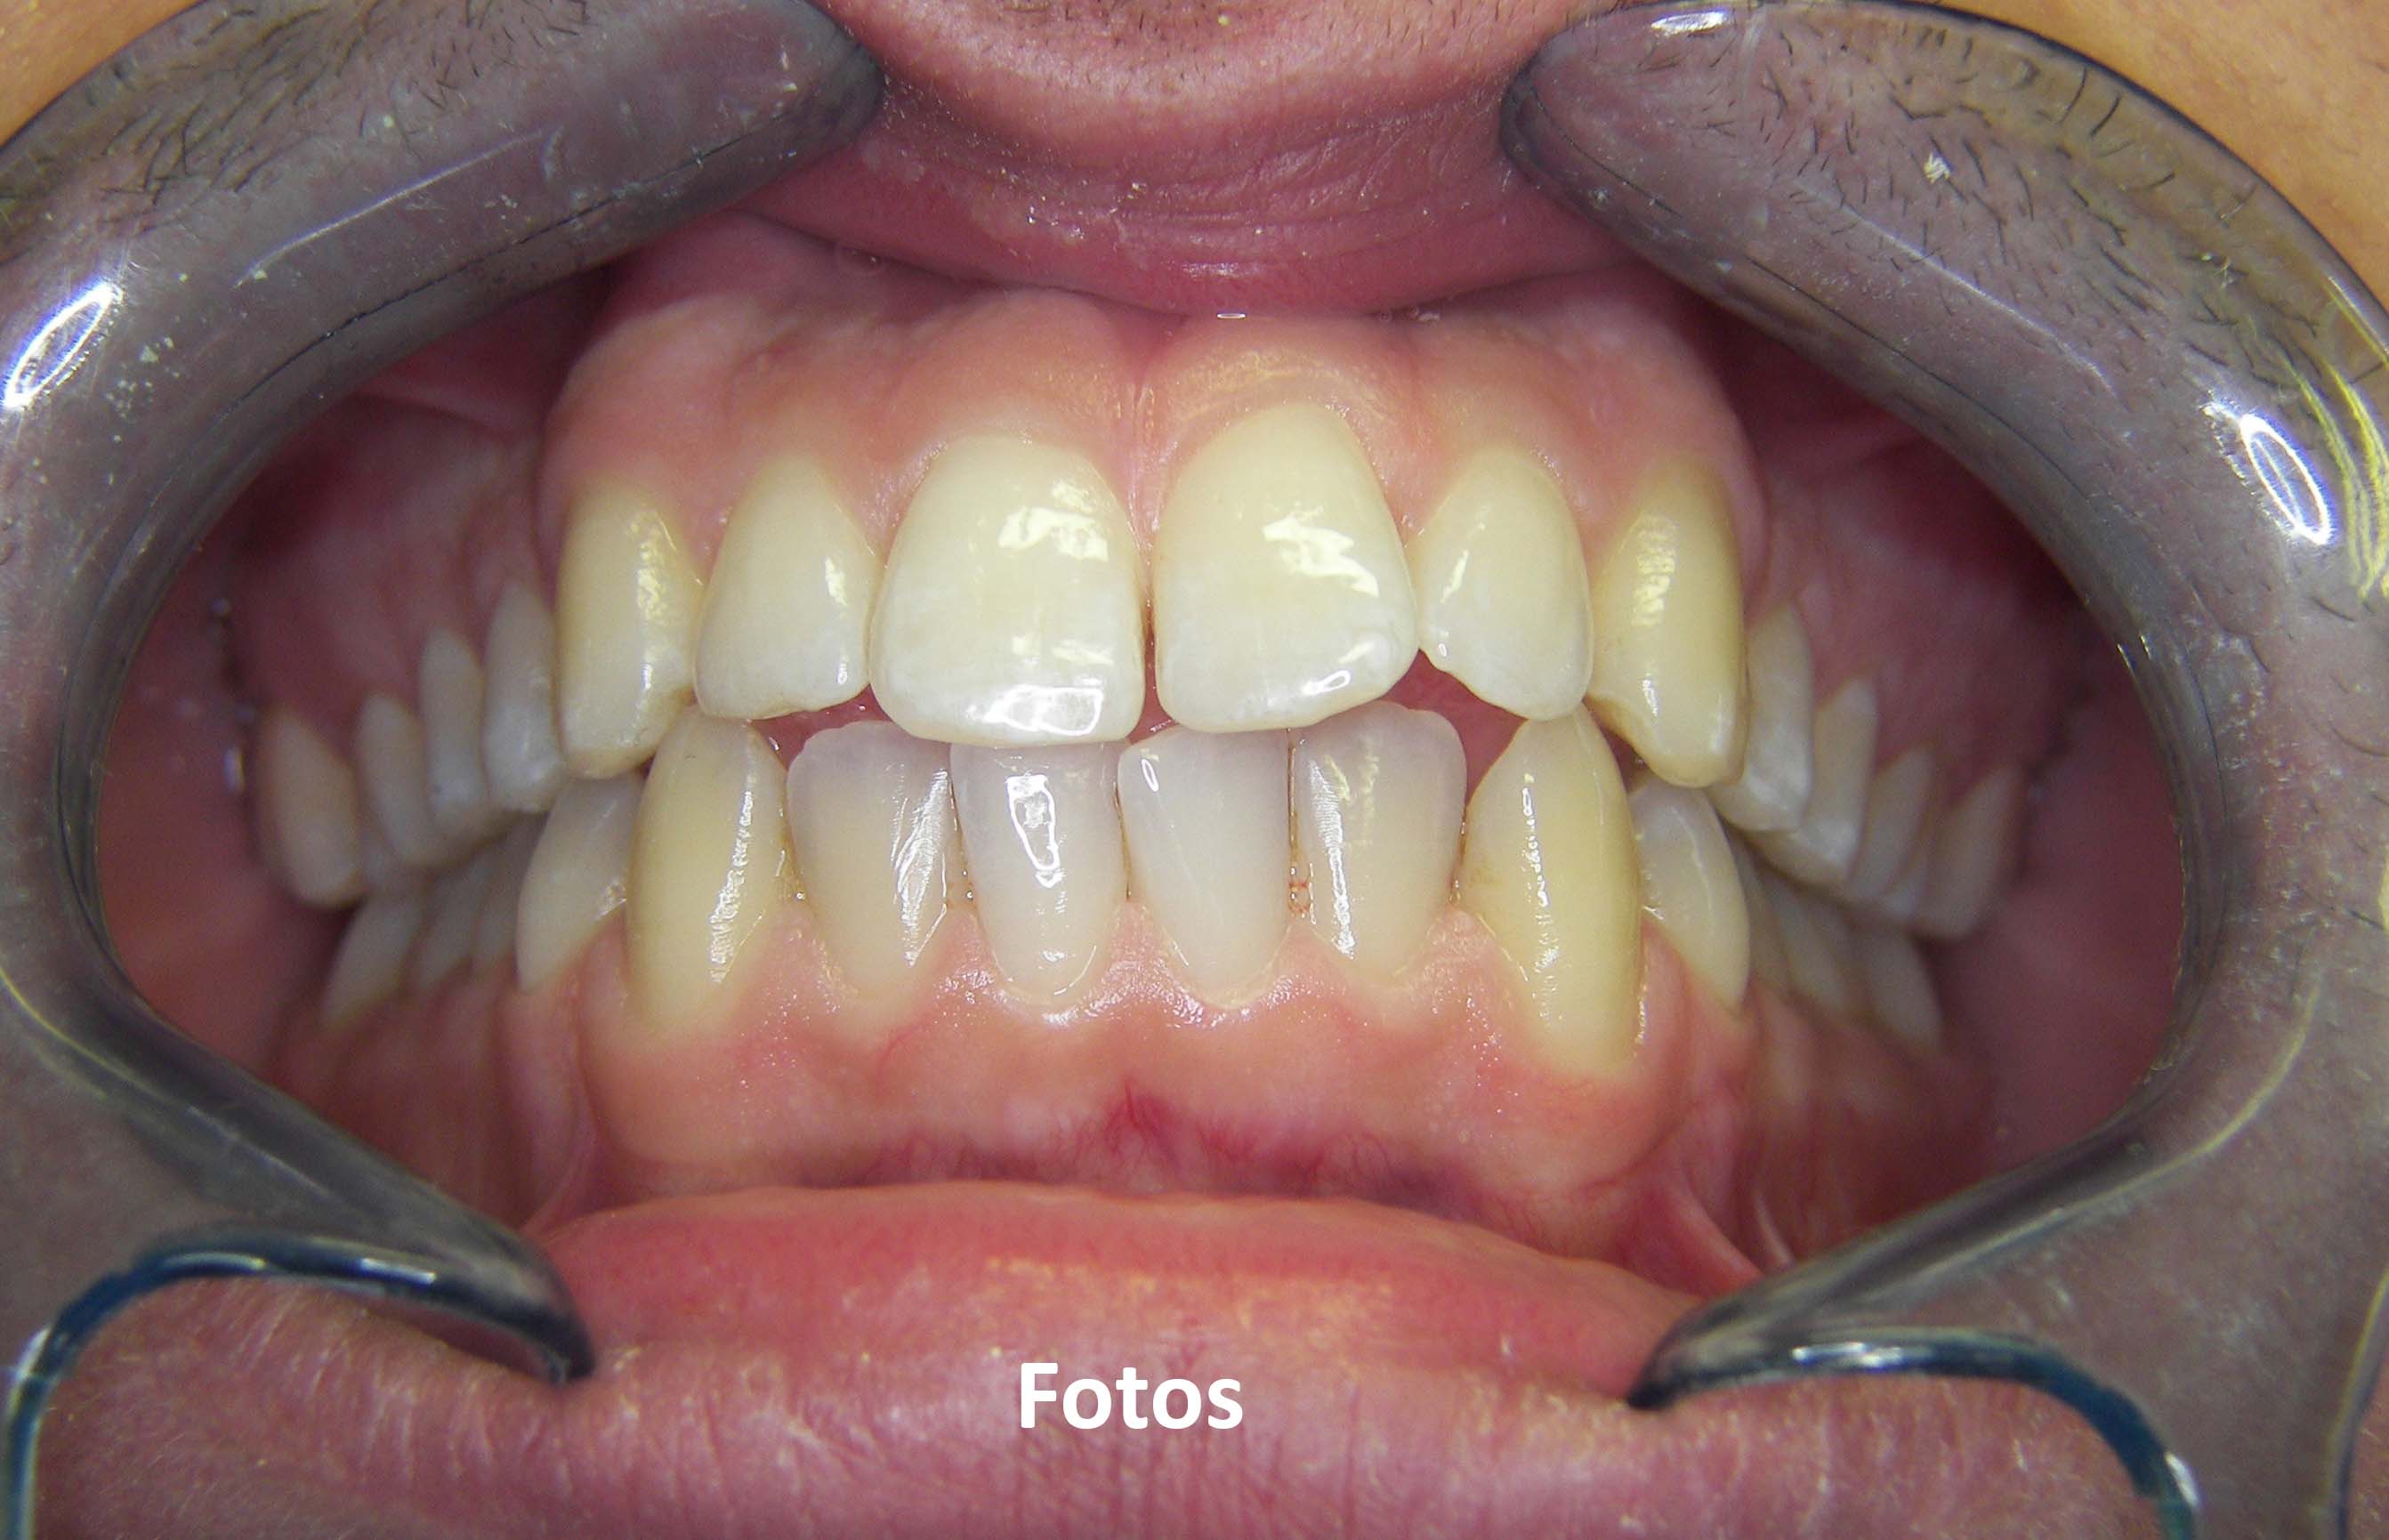

3. Fotografias

Tratamentos urgentes serão executados se necessário, como no caso à esquerda.